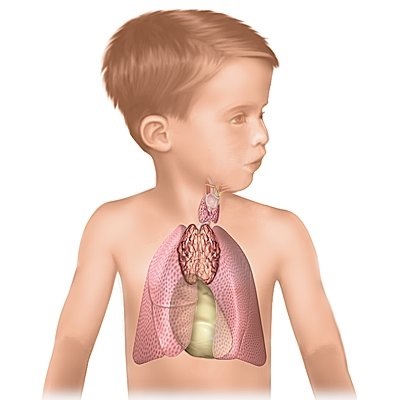

A leggyakoribb a csecsemők, egyre inkább patológiai a csecsemőmirigy, vagy Thymomegalia.

Thymomegalia - hyperplasia a csecsemőmirigy és annak alulműködése kísérő számos gyermekkori betegségek. Gyermekek thymomegaly ajánlott egészségügyi építési tevékenységek, vesz egy multivitamin, a bio-stimulánsok; a vallomása - glükokortikoszteroidok.

Általában thymomegaly tüneteket figyeltek meg a gyermekek akár 3-6 évig. Ezt követően, azok vagy eltűnnek, vagy átalakítják más betegségek. Thymomegalia gyermek képviseli a proliferációját thymus (csecsemőmirigy).